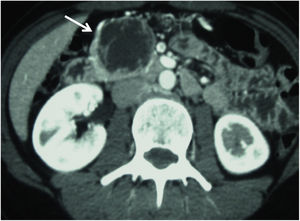

The preoperative study of the patients was carried out with imaging techniques, such as abdominal computed tomography (CT) scans (Fig. 1) and magnetic resonance cholangiopancreatography (MRCP)/magnetic resonance imaging (MRI) of the pancreas and octreotide scan in cases of neuroendocrine tumor (NET). In some patients, endoscopic retrograde cholangiopancreatography (ERCP) and endoscopic ultrasound (EUS) were necessary to obtain a preoperative biopsy. Duodenal and vascular involvement, both venous and arterial, as well as proximity of the lesion to the Wirsung duct, were ruled out preoperatively.

Given that UC is not considered oncological surgery, the main challenge of this surgical strategy is meticulous patient selection to rule out lesions with a high probability of having invasive behavior. Therefore, precise preoperative studies should include abdominal CT scan and pancreatic MRCP/MRI for the characterization of these lesions and assessment of their relationship with surrounding structures. ERCP and EUS, which are associated with bleeding, are considered second-line techniques for the diagnosis of lesions located in the UP, the latter being essential if biopsies are required.